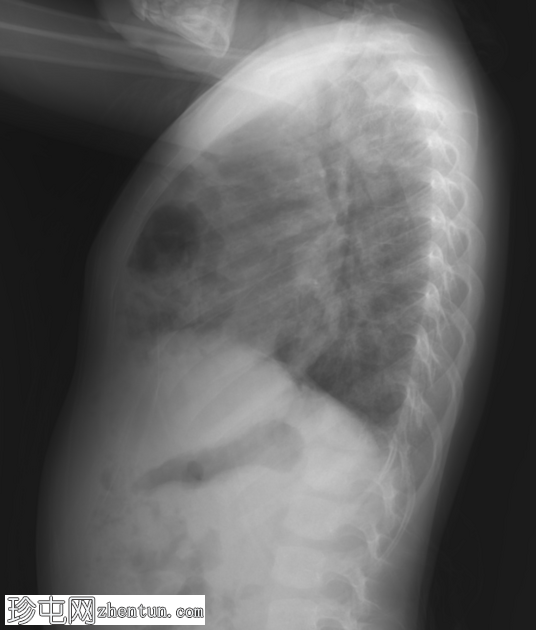

CT

3.png

冠状位增强扫描

动脉期

4.png

轴位增强扫描

5.png

矢状位增强扫描

横结肠及其系膜经膈前部缺损疝入前纵隔。

未见肠管扩张或梗阻。

双肺实变影,提示呼吸道感染。